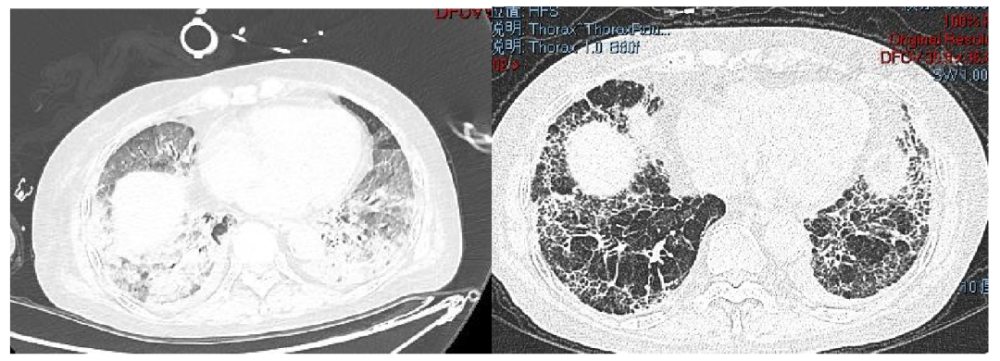

肺纖維化高發

《Nature Medicine》2021年發表了“Post-acute COVID-19 syndrome”,研究指出呼吸困難在60-100天的隨訪期內的發生率為42%-66%,有6.6%的患者因持續低氧血癥需要補充氧氣?;颊叱鲈汉?個月評估發現約25%的輕度至中度病例存在纖維化,在重癥病例居多的隊列中,約65%的康復者存在肺纖維化。